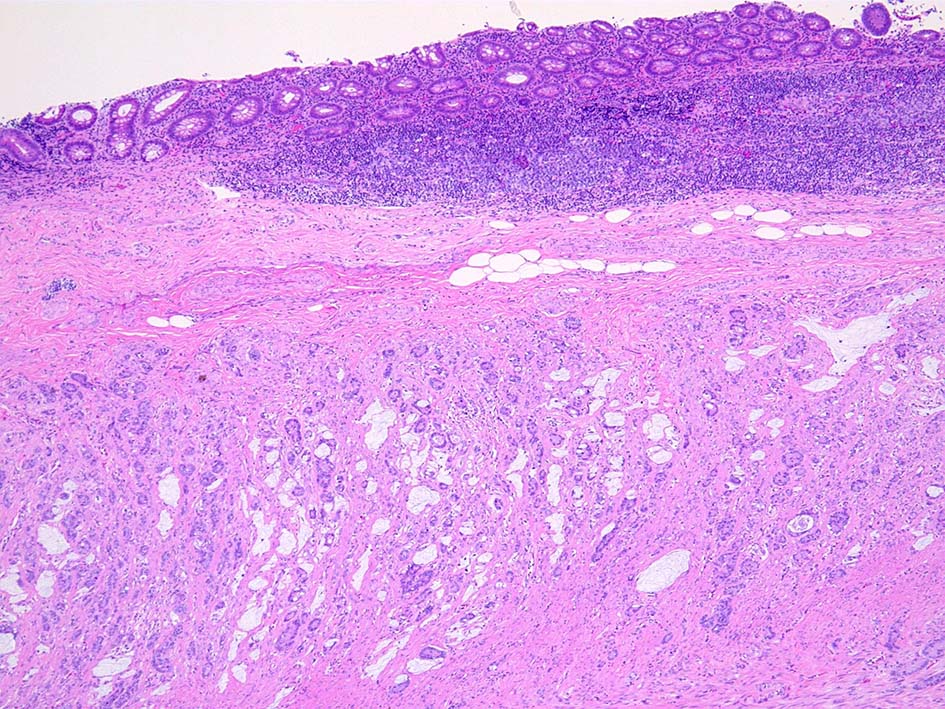

31歳 女性 X年4月下腹部痛で虫垂炎と診断され保存的治療をおこなう. 同年 7月手術を希望し腹腔鏡下虫垂切除術が施行される.

虫垂肉眼所見

虫垂末梢側で壁が肥厚している. 糞石はない.

組織所見